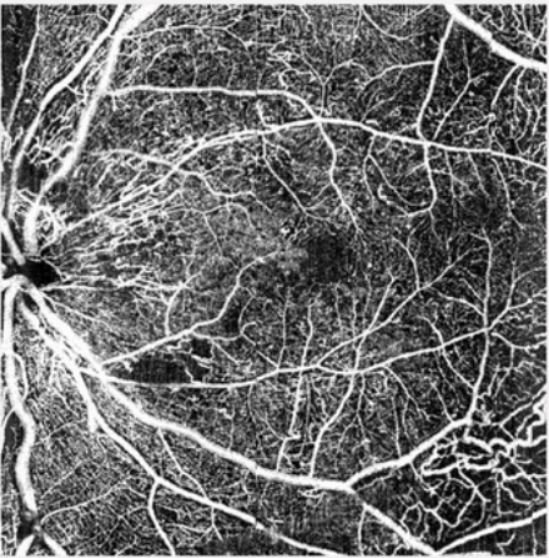

Ultra-high resolution, wide-angle imaging Clear visualization of ocular fundus vessels

Fundus exploration at a glance

Acquisition image resolution up to 8K

High Speed 86, 000 A scan per second